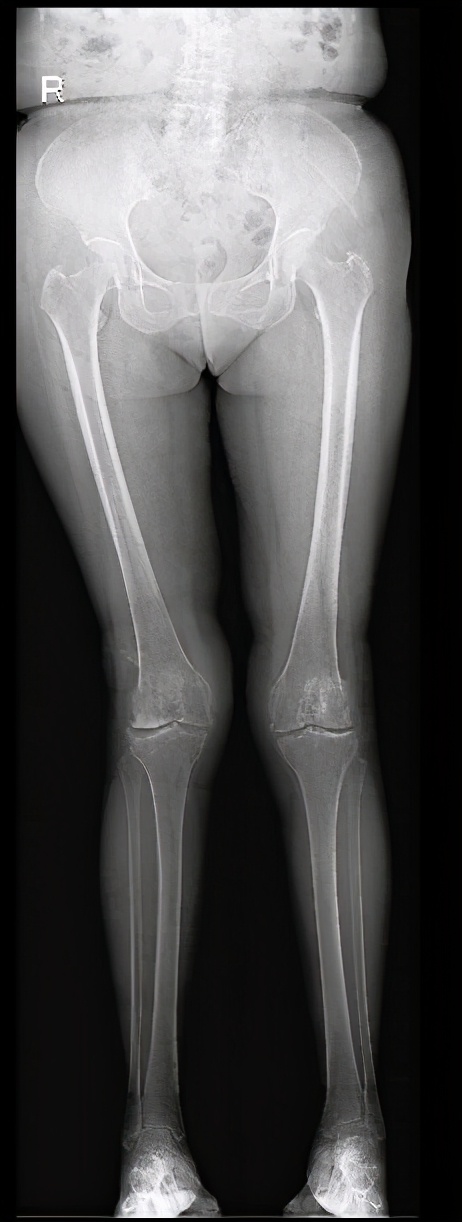

图6 膝骨关节炎内侧单髁置换术:a术前

图6 膝骨关节炎内侧单髁置换术:b术后

图6 :a图显示右侧膝关节内侧间室退变磨损严重(亦即疼痛所在部位),b图显示内侧单髁置换术后